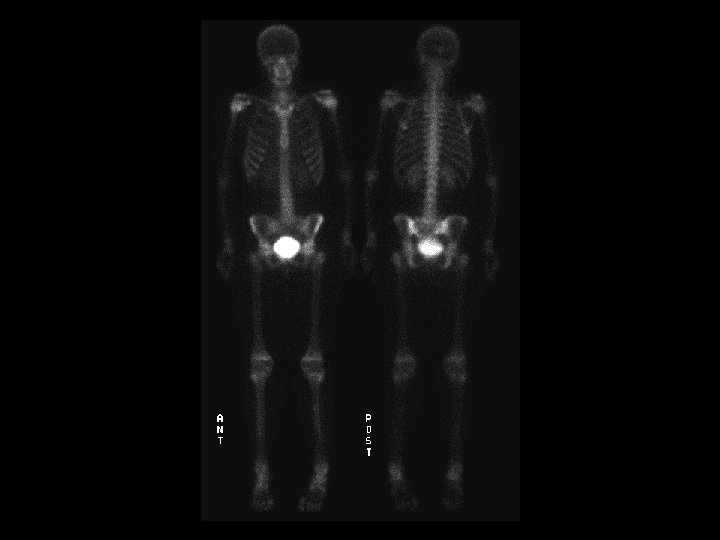

Sickle cell anemia • Findings: – Bone scan shows increased activity in the kidneys, a small spleen, and knees • ddx: – NONE! – This is an Aunt Minnie!